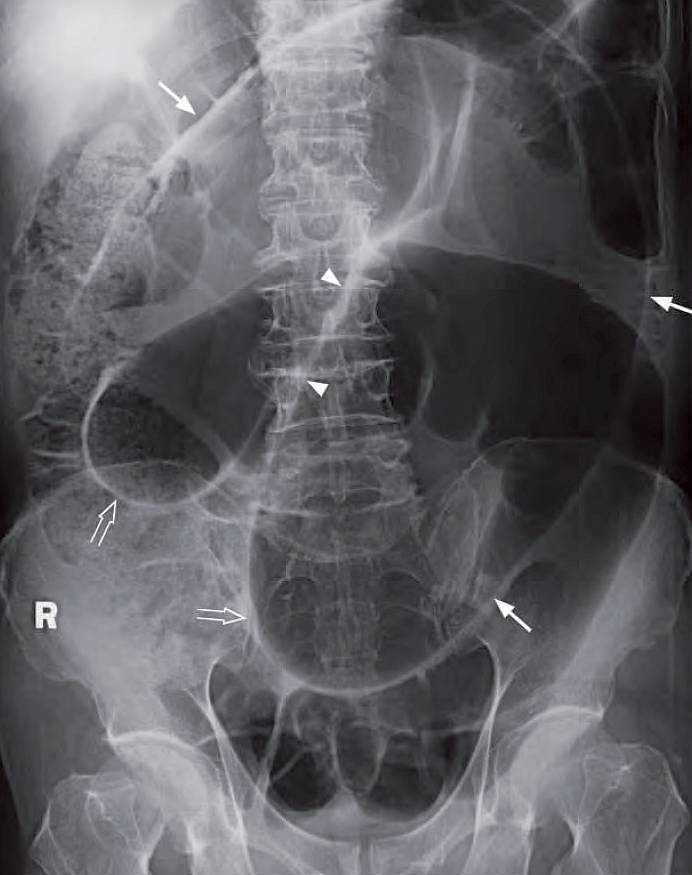

- Massively distended bowel with inverted U-shaped configuration – representing a grossly dilated sigmoid colon.

- ‘Coffee-bean sign’ – distinct midline crease between the distended loop. It represents the two bowel walls in contact.

- Inferior convergence sign – the two limbs of the loop converge inferiorly, pointing to the left lower quadrant.

Supine abdominal radiograph shows grossly dilated sigmoid colon (arrows) with the ‘coffee bean’ sign (arrowheads) and inferior convergence sign of sigmoid volvulus (open arrows).